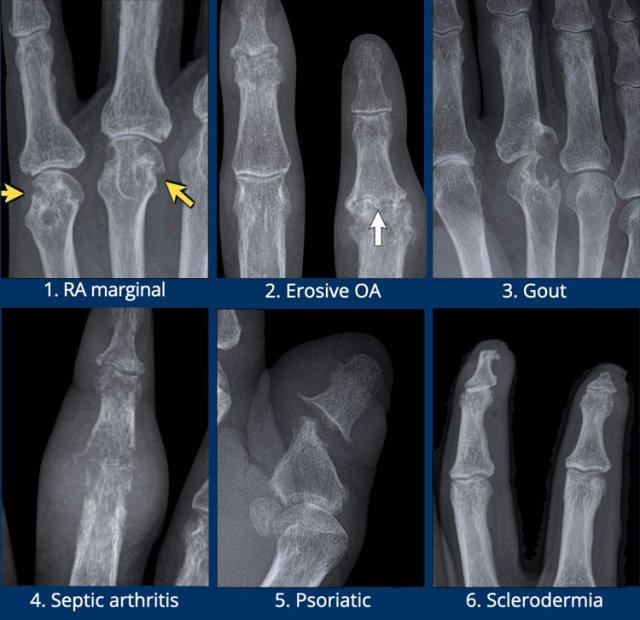

Các ví dụ điển hình về các dạng bào mòn đặc trưng

- Viêm khớp dạng thấp.

Bào mòn bờ khớp điển hình tại các khớp MCP. - Viêm xương khớp bào mòn.

Bào mòn xương dưới sụn tại các khớp DIP và PIP. Sự hình thành đồng thời của gai xương tạo ra biến dạng cánh hải âu. - Bệnh gout.

Bào mòn lệch tâm với bờ nhô ra. Bờ xơ cứng trong trường hợp này cho thấy bệnh mạn tính và tiến triển chậm. - Nhiễm trùng.

Tổn thương phá hủy kèm mất sụn và bào mòn xương. - Viêm khớp vảy nến.

Bào mòn xương thu hẹp đầu đốt ngón gần thành hình “bút chì”, tựa vào “cốc” được tạo bởi nền đốt ngón xa mở rộng do tăng sinh xương. - Xơ cứng bì.

Và các rối loạn đa hệ thống khác có thể gây bào mòn tại các chỏm đốt ngón xa, tình trạng này được gọi là tiêu xương đầu chi (acro-osteolysis).